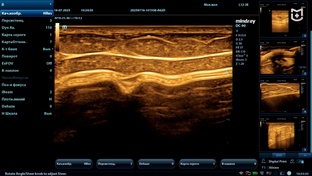

06:171,0×00:00/06:17ПодборкаMEDLIGA - поставка медицинского оборудования1377 смотрели · 3 года назадПодписатьсяУЗИ молочных желез и анализ образований по BI-RADS на Mindray Resona i9